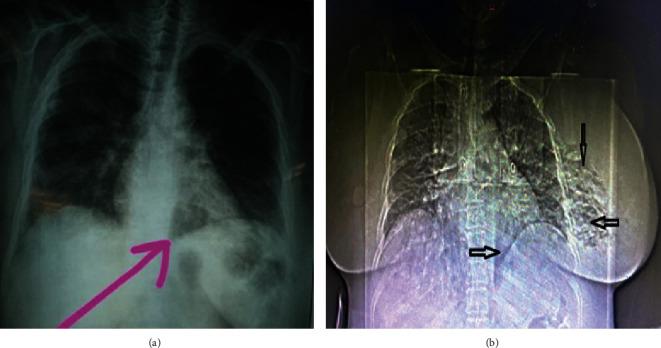

乳腺坏死性软组织感染:一种潜在致命的外科急症。

Necrotizing Soft Tissue Infections of the Breast: A Potentially Lethal Surgical Emergency.

Necrotizing soft tissue infection (NSTI) of the breast is an extremely rare event in surgical practice. It is considered the most aggressive form of soft tissue infection and a true surgical emergency. It is also associated with a high risk of mortality if not diagnosed promptly. Few cases have been documented in the literature; the exact etiology and risk factors vary from those involving the limbs, trunk, and perineum. Early recognition, prompt surgical treatment, and broad-spectrum antibiotic therapy are crucial for reducing morbidity and mortality. These reports present cases of NSTIs in breasts with unique etiologies and challenges in their management.

乳腺坏死性软组织感染(NSTI)在外科实践中是极为罕见的情况。它被认为是软组织感染最具侵袭性的形式,也是真正的外科急症。如果不能及时诊断,还会伴有高死亡率风险。文献中记录的病例很少;其确切病因和风险因素与涉及四肢、躯干和会阴的情况有所不同。早期识别、及时的手术治疗和广谱抗生素治疗对于降低发病率和死亡率至关重要。这些报告展示了具有独特病因及治疗挑战的乳腺NSTI病例。